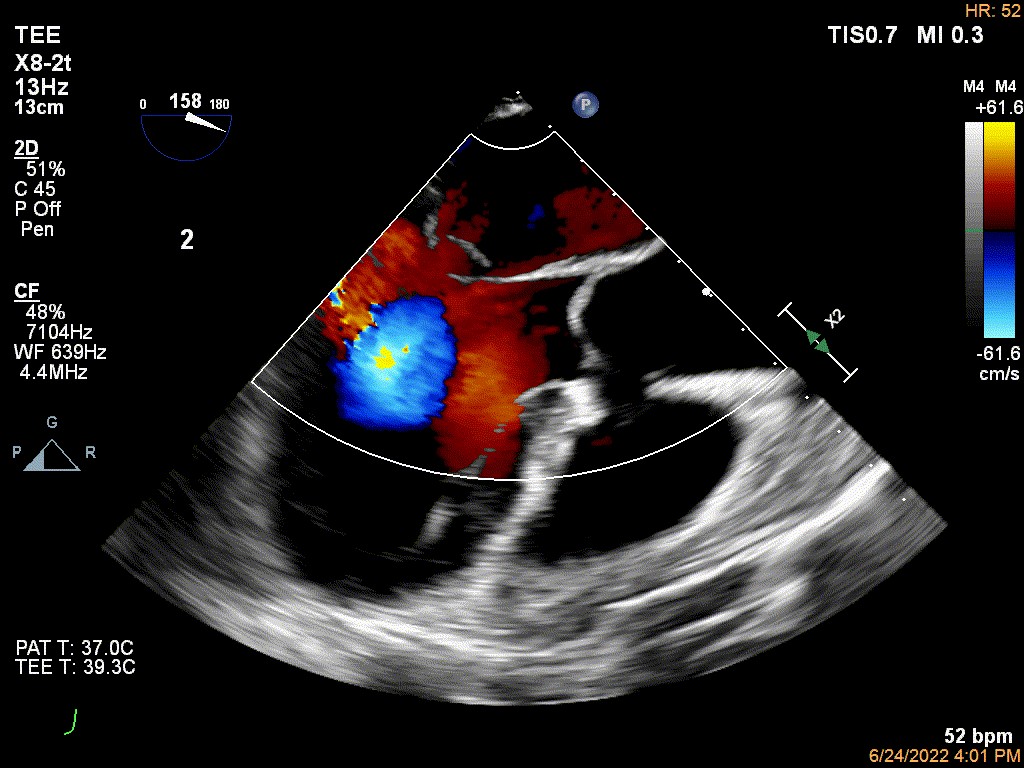

术前食道超声示二尖瓣大量偏心反流

术前食道超声示二尖瓣大量偏心反流,腱索断裂伴后瓣脱垂

患者是一名79岁男性。主诉劳力性呼吸困难反复发作3月,入院心电图显示窦性心律,心率71次每分。冠脉造影提示患者前降支和右冠状动脉粥样斑块,未见明显狭窄。心脏彩超LVEF 65.0%,LVEDD 61mm,二尖瓣重度偏心重度反流,腱索断裂,后瓣脱垂,VC 6.1mm,EROA 1.0cm²,Rvol 130ml,二尖瓣环面积5.8cm²。